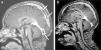

The patient had normal blood pressure; however, bilateral papilledema was detected. Magnetic resonance imaging (MRI) showed hyperintense thrombosis in the superior sagittal sinus and in both proximal segments of transverse sinuses (Fig. 1a). Subcutaneous low-molecular-weight heparin (LMWH) was started. The patient was investigated for a prothrombotic state and a methylenetetrahydrofolate reductase (MTHFR) heterozygous mutation was found. Azathioprine was added. One month later bilateral papilledema was detected again. The brain MRI was repeated and a new thrombosis distal to the superior sagittal sinus was detected. After permission from the ministry of health, infliximab was used at a 5mg/kg/day dose and 3 doses were applied on the 0, 2 and 6 weeks. Before the infliximab, azathioprine was stopped; prednisolone was tapered and stopped at the 7th day of infliximab. Ten days after first dose of infliximab, C-reactive protein was decreased to normal range, and both frequency and severity of the oral aphthous lesions were reduced. Resolution of the thrombosis was seen after the second dose of infliximab in the brain MRI (Fig. 1b). Ongoing therapies consist of colchicine and LMWH. Infliximab was well tolerated by this patient; no drug-induced side effects were recorded.

(a) Magnetic resonance imaging of brain before the infliximab. Hyperintense thrombosis filling the superior sagittal sinus and proximal segments of both transverse sinuses was showed and (b) after second dose of infliximab, significant dissolution of the thrombosis was observed in the brain MRI.